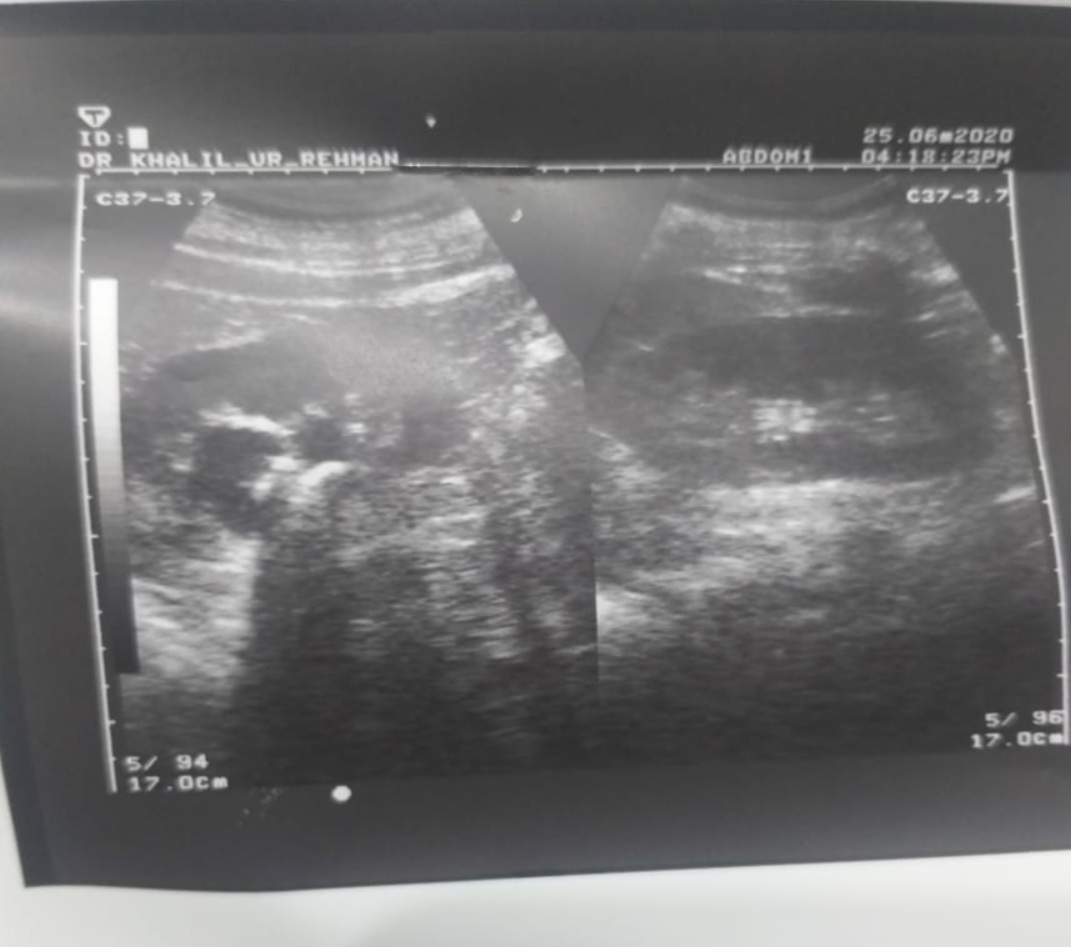

Assalam o alaikum sir 3 months ago my father has a severe pain on his kidneys when we ultrasound the kidneys there are multiple stones on both sometime blood come with urine plz guide me what we should do and which kind of test we should do.